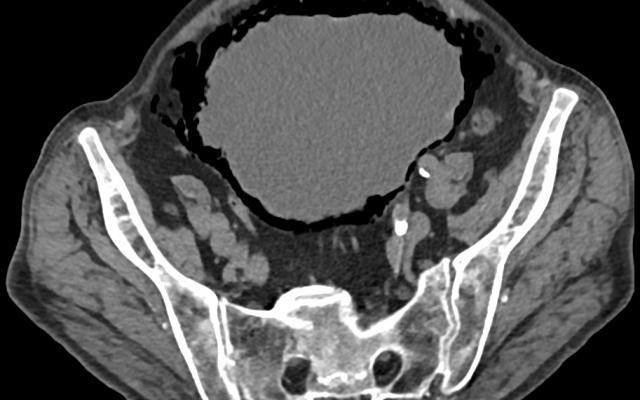

Actinomycosis van het kleine bekken